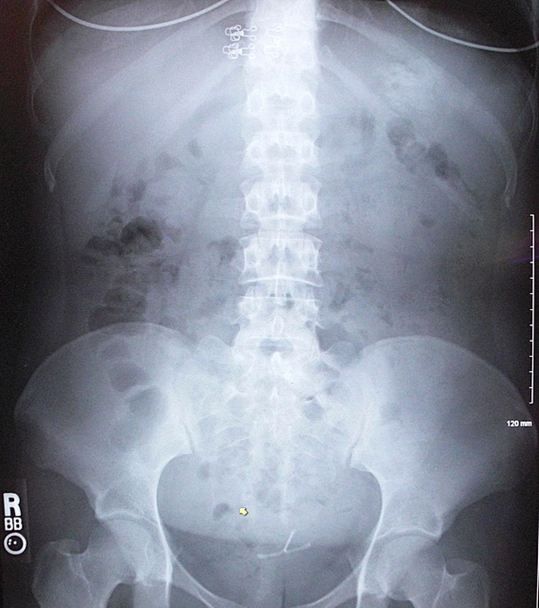

The plain film of the abdomen is shown in the Figure, above right; click image to enlarge.

Note the slightly hyperdense, somehwhat circular mass in the left upper quadrant just below the bra wire. This is a vegetable matter bezoar. An IUD is incidentally seen in the pelvis but is not related to her symptoms (nor are her 2 bra wires and 8 bra clasps). The bowel gas pattern is nonobstructive.